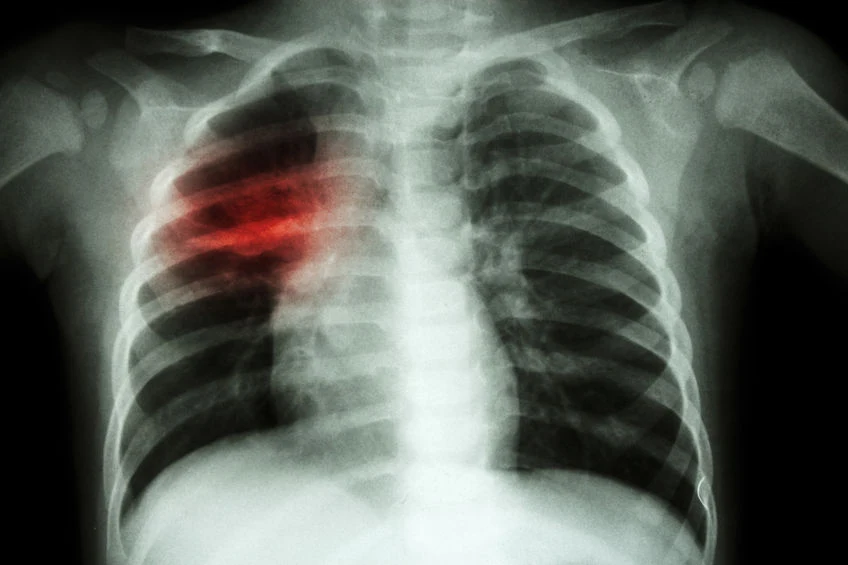

Gruźlica to potencjalnie śmiertelna choroba zakaźna wywoływana przez prątka gruźlicy (Mycobacterium tuberculosis), która dotyka najczęściej płuc (szacuje się, że gruźlica pozapłucna stanowi zaledwie 8,8 proc. wszystkich przypadków), więc do większości zakażeń dochodzi drogą kropelkową. Do wywołania choroby potrzebna jest też stosunkowo duża ilość prątków, więc znacznie ma tu długość i bliskość kontaktu z chorym, a także wentylacja pomieszczenia.

A jakie objawy powinny zwrócić naszą uwagę? Uporczywy kaszel, który trwa dłużej niż trzy tygodnie i zwykle powoduje odkrztuszanie flegmy (także krwawej), pogarszające się duszności, brak apetytu i utrata masy ciała, wysoka temperatura, nocne poty oraz skrajne zmęczenie lub znużenie. Same w sobie nie są wystarczające do postawienia diagnozy, ale powinny skłonić do szukania pomocy lekarskiej i dalszej diagnostyki (diagnostyka mikrobiologiczna).